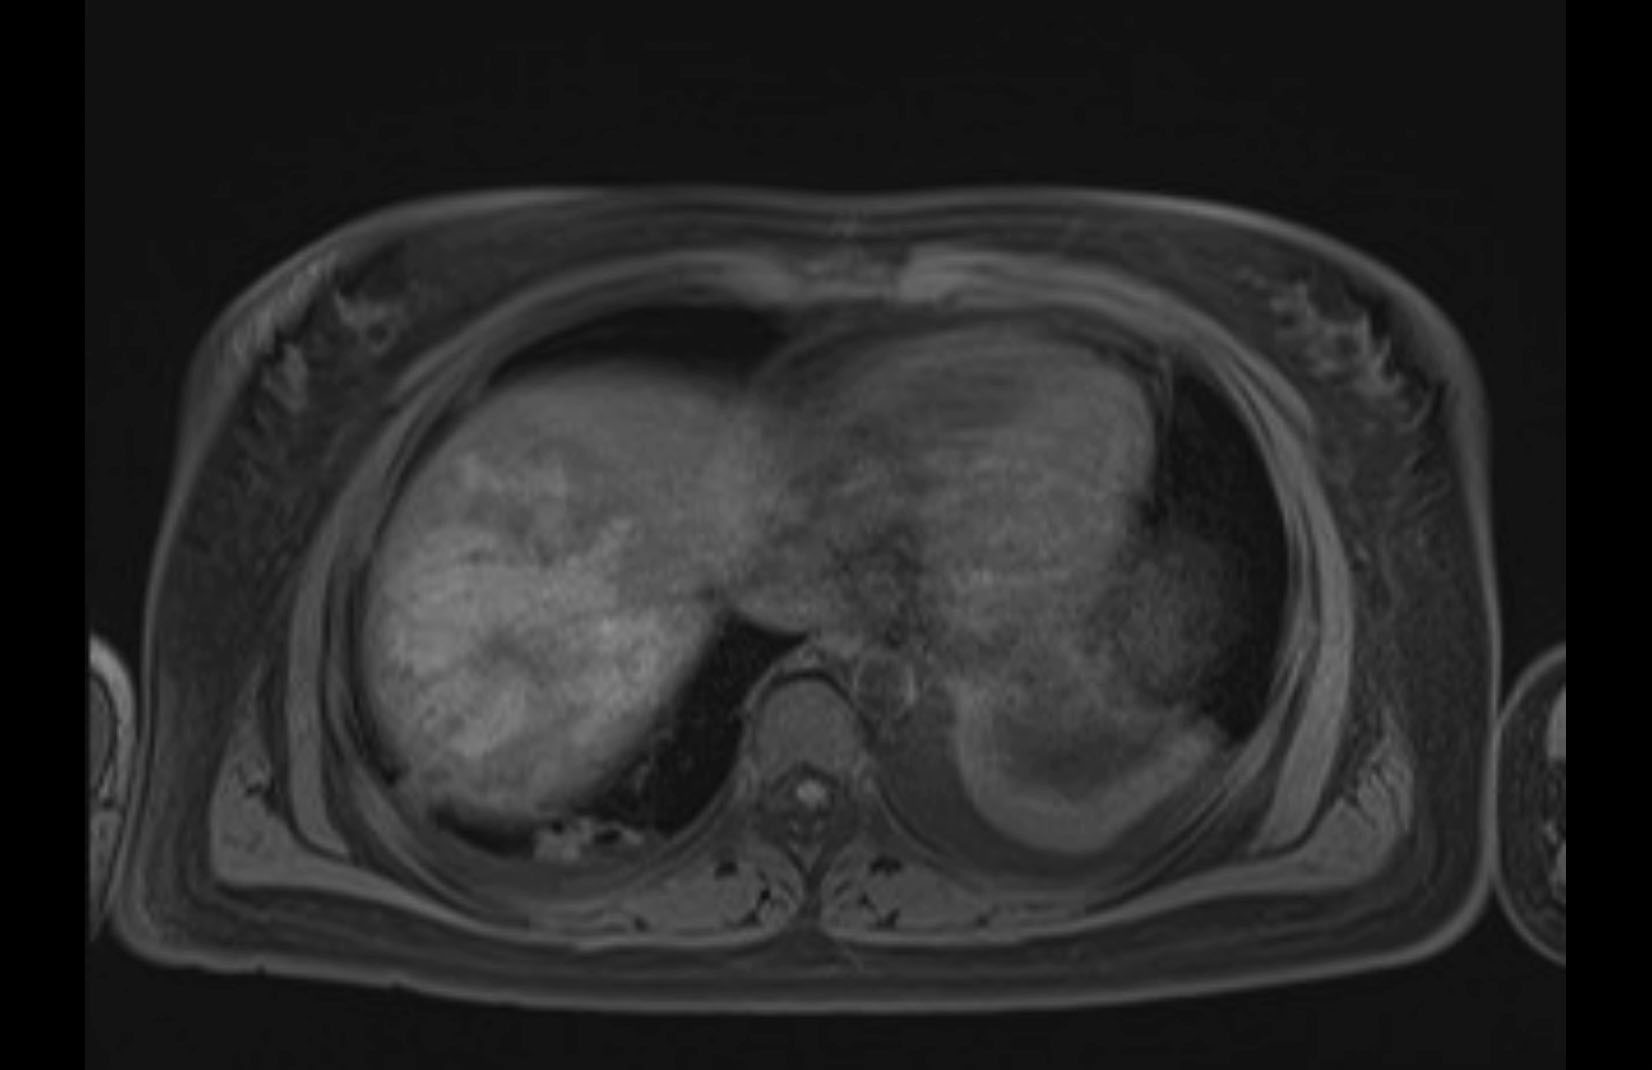

Imaging Analysis

Look through the patient's CT scan to identify any areas of concern for the necessary procedure.

MRI T1

Based on initial findings, which issue(s) would you be most concerned about?